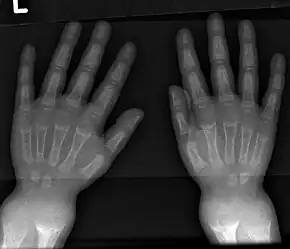

An X-ray or radiograph of an advanced sufferer from rickets tends to present in a classic way: the bowed legs (outward curve of long bone of the legs) and a deformed chest. Changes in the skull also occur causing a distinctive "square headed" appearance known as "caput quadratum".[14] These deformities persist into adult life if not treated. Long-term consequences include permanent curvatures or disfiguration of the long bones, and a curved back.[15]

- Radiography typically show widening of the zones of provisional calcification of the metaphyses secondary to unmineralized osteoid. Cupping, fraying, and splaying of metaphyses typically appears with growth and continued weight bearing.[36] These changes are seen predominantly at sites of rapid growth, including the proximal humerus, distal radius, distal femur and both the proximal and the distal tibia. Therefore, a skeletal survey for rickets can be accomplished with anteroposterior radiographs of the knees, wrists, and ankles.[36]